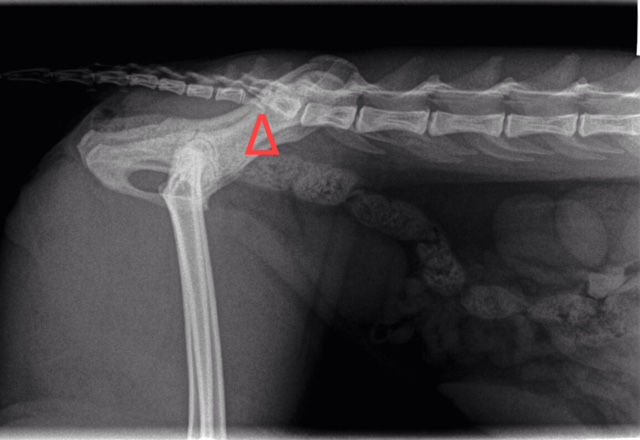

My Cat Has Had A Broken Tail Since Birth Finally Got An X Ray Done On It A Few Years Later Doesn T Cause Her Pain Or Anything Vet Never Saw It As A

The cats tail primarily is used for communication. Cat broken tail xray Friday August 26 2022 Edit. Any form of tail trauma merits a full x-ray investigation.

When you and your vet have decided on a treatment plan allow your vet to do what is necessary to treat the fracture. However if the cat needs to be in a complicated position for the x-ray or is aggressive or when. This will reveal the extent of any damage and ensure the cat gets the right treatment.

A noticeable kink or break in the tail. The tail being extremely painful to touch. The xray confirmed she has a 14 separation at the s1.